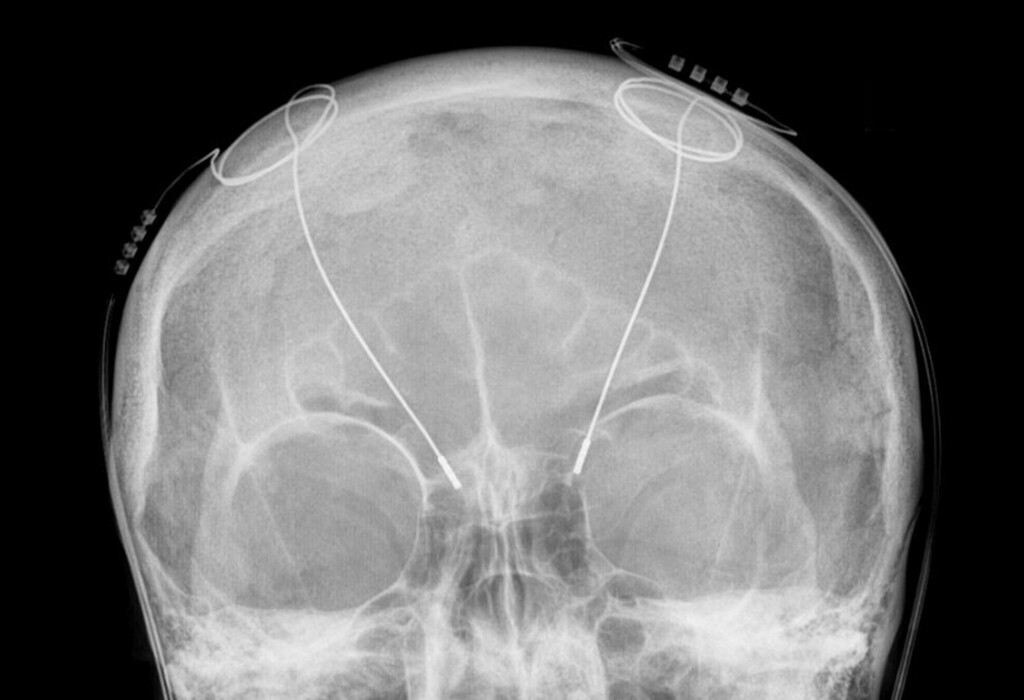

Der fernsehbeitrag verfolgt das patientenschicksal vor während und nach der. Dabei werden sonden in bestimmte zerebrale hirnkerne eingebracht und anschließend über einen hirnschrittmacher stimuliert. Hirnschrittmacher sind eine große hilfe für tremorpatienten. Beispiel einer erfolgreichen operation zur tiefen hirnstimulation bei dystonie.

ärzte der hamburger uni klinik eppendorf setzen parkinson patienten einen hirnschrittmacher ein.